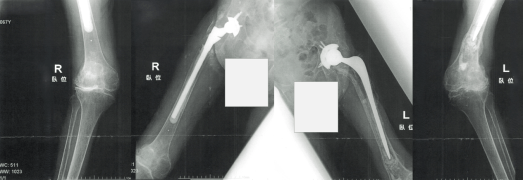

Hさん(関節リウマチ、両股関節障害、化膿性狭心症、化膿性関節炎など)へのリハビリとしては、足関節の可動域の向上と下肢筋力の強化としていました。